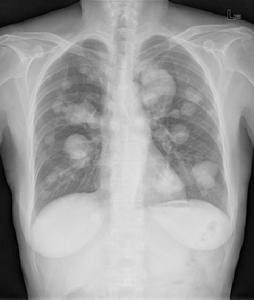

(1)血行肺轉移瘤X線提示 ①兩肺多發大小不等的球形病灶,邊緣光滑,密度均勻,多見於中下肺野。②兩肺廣泛瀰漫性粟粒狀陰影,邊界模糊。③單個較大的結節病灶,邊緣光整,呈分葉狀,密度均勻,最多見於結腸癌。④可發生空洞或鈣化,空洞以頭頸及生殖系統的鱗癌多見,鈣化多見於骨肉瘤、軟骨肉瘤。⑤可發生自發性氣胸,骨肉瘤或纖維肉瘤多見。⑥極少數表現為肺動脈高壓。⑦肺炎型轉移罕見,表現為片狀模糊影,乳腺癌多見。⑧支氣管轉移罕見,常見於腎癌和結腸,表現為支氣管狹窄及阻塞徵象。

CT是發現小轉移灶或評價縱隔轉移的最有效的方法。結節多見於下葉的外1/3,距胸膜表面3厘米以內。空洞、鈣化更易發現。高分辨力CT薄層掃描顯示肺間質呈網狀改變,伴細小結節,小葉間隔不規則增厚。